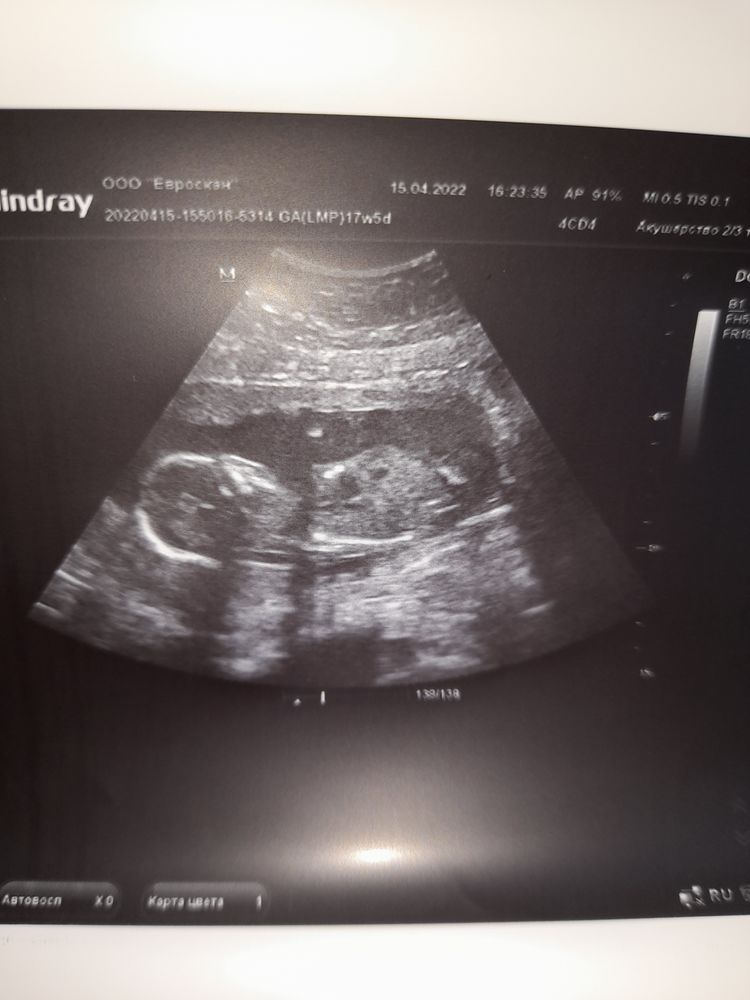

17+5 недель счастья🙏🥰😊

Сходила на узи плановое к своей Г. Идем в срок🙏 цервик.канал=45мм,плацента выше внутр.зева на 7см😊в общем ПАчиться нам можно🤭🤭🤭

Ну и конечно,у нас 100% подтвердили доченьку💃💃💃💕💕💕Малышка сейчас лежит ножками вниз,врач сказала,что может пинать мочевой🤔я и думаю,часто бегаю в тубзик,особенно ночью🤭

Всем планюшам желаю увидеть свои заветные //🙏 ну и немного нашей дамочки🥰